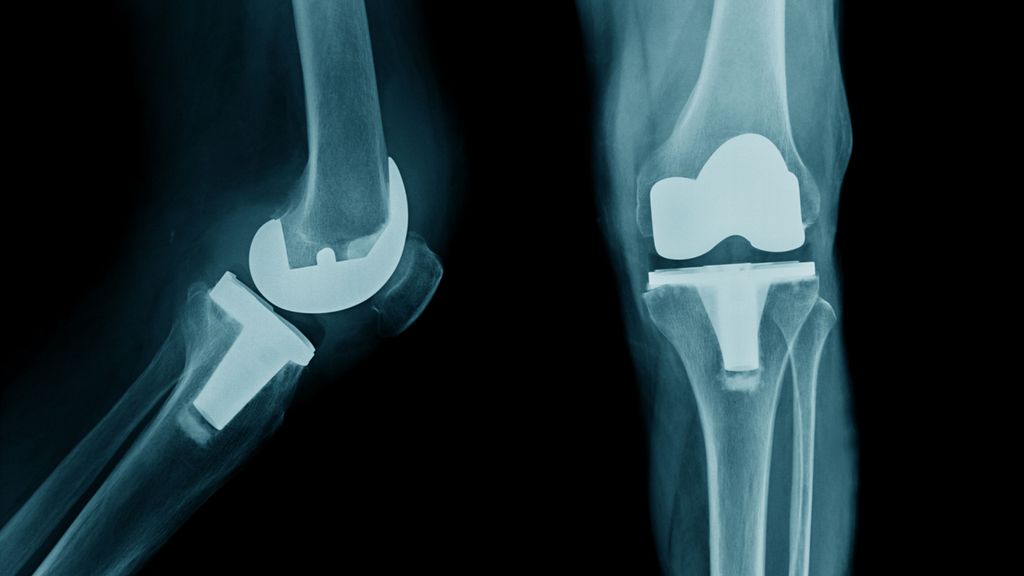

Zu Beginn und am Ende des dreiwöchigen Aufenthalts wurden Messungen im Ganglabor durchgeführt (Abb.1). Diese beinhalteten 3D-Videoaufnahmen des Gangbilds zur Erfassung der Gangparameter (Gehgeschwindigkeit, Schrittlänge, Doppelschrittlänge, Kadenz und Spurbreite) und des Kniewinkelverlaufs sowie die Messung der vertikalen Bodenreaktionskraft, die mit Kraftmessplatten erfasst wurde. Zudem wurde mittels Elektromyografie (EMG) die Muskelaktivität des M. tibialis anterior und des M. gastrocnemius lateralis gemessen. Zusätzlich wurde eine subjektive Perspektive der Patient:innen zur Schmerzsituation, Steifheit und Funktion des künstlichen Knies sowie zur Orthese mittels Fragebogen erfasst.

Abb. 1: Initialer Fersenkontakt (IC) und „loading response“ (LR) im Gangzyklus mit/ohne FES-Orthese und EMG